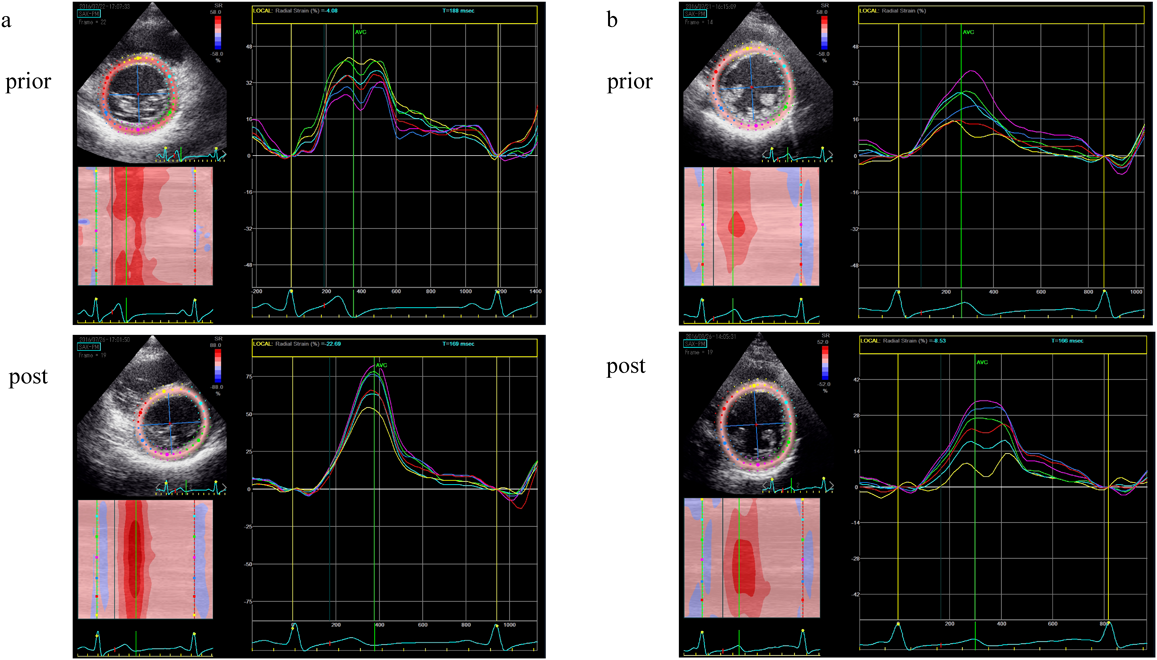

Wolff–Parkinson–White症候群における心室早期興奮が心機能に及ぼす影響Effect of Ventricular Preexcitation on Left Ventricular Function in Pediatric Patients with Wolff–Parkinson–White Syndrome